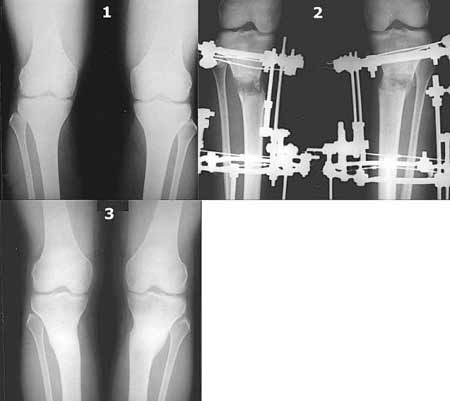

Картинки - в приложении.Будут вопросы - готов ответить.

Ещё картинка - схема. Хотя у Соломина всё написано.

Вот ещё картинки, которые отправлял в Ортопод. Коррекция кривизны и удлинение на 3 см.